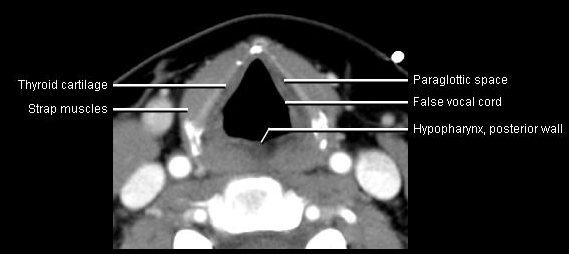

Phonation and dysphagia involve multiple coordinated structures in the larynx and pharynx. Radiation induced dysphagis appears to be related to dose to the phyaryngeal constrictor muscles and specific regions of the supraglottic and glottin larynyx.

Speech is impacted by doses to the epiglottis, base of tongue, aryepiglottic folds, false vocal cords upper esophageal sphincter and cricoid cartilage.